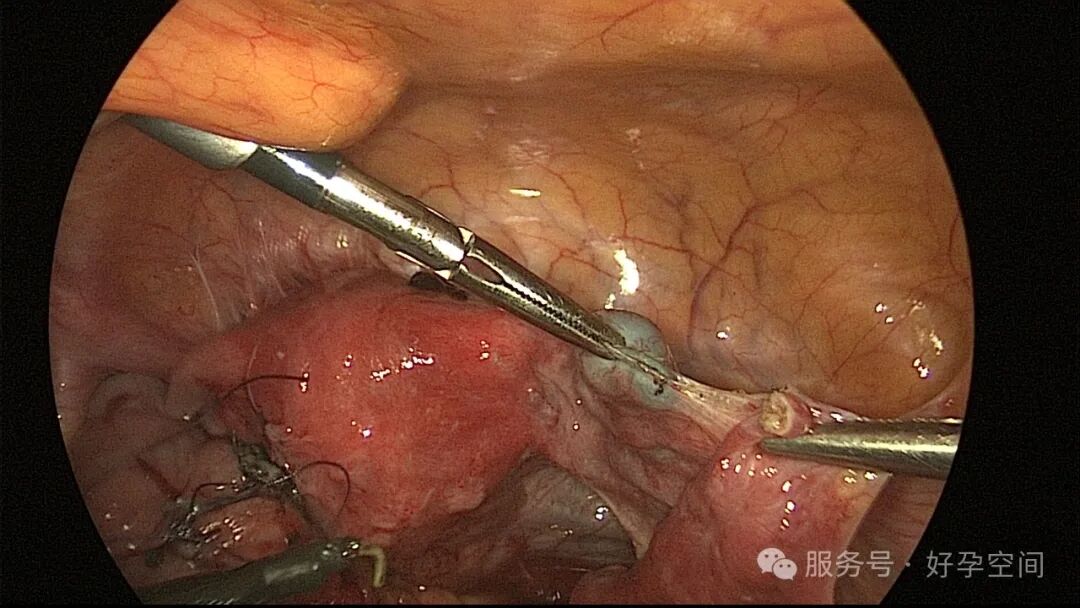

病例3:35岁,原发不孕13年。2020年11月子宫输卵管造影提示左侧输卵管积水,右侧输卵管壶腹部堵塞。2020年12月手术,左侧输卵管伞端造口成形,右侧输卵管壶腹部先天性离断,输尿管导管做支架,行端端吻合术,美蓝通液双侧输卵管均见美蓝液流出。2021年7月自然妊娠,孕17+2周要求引产,住院2天被劝出院,放弃引产。孕17+5周再次住院,坚决要求引产。